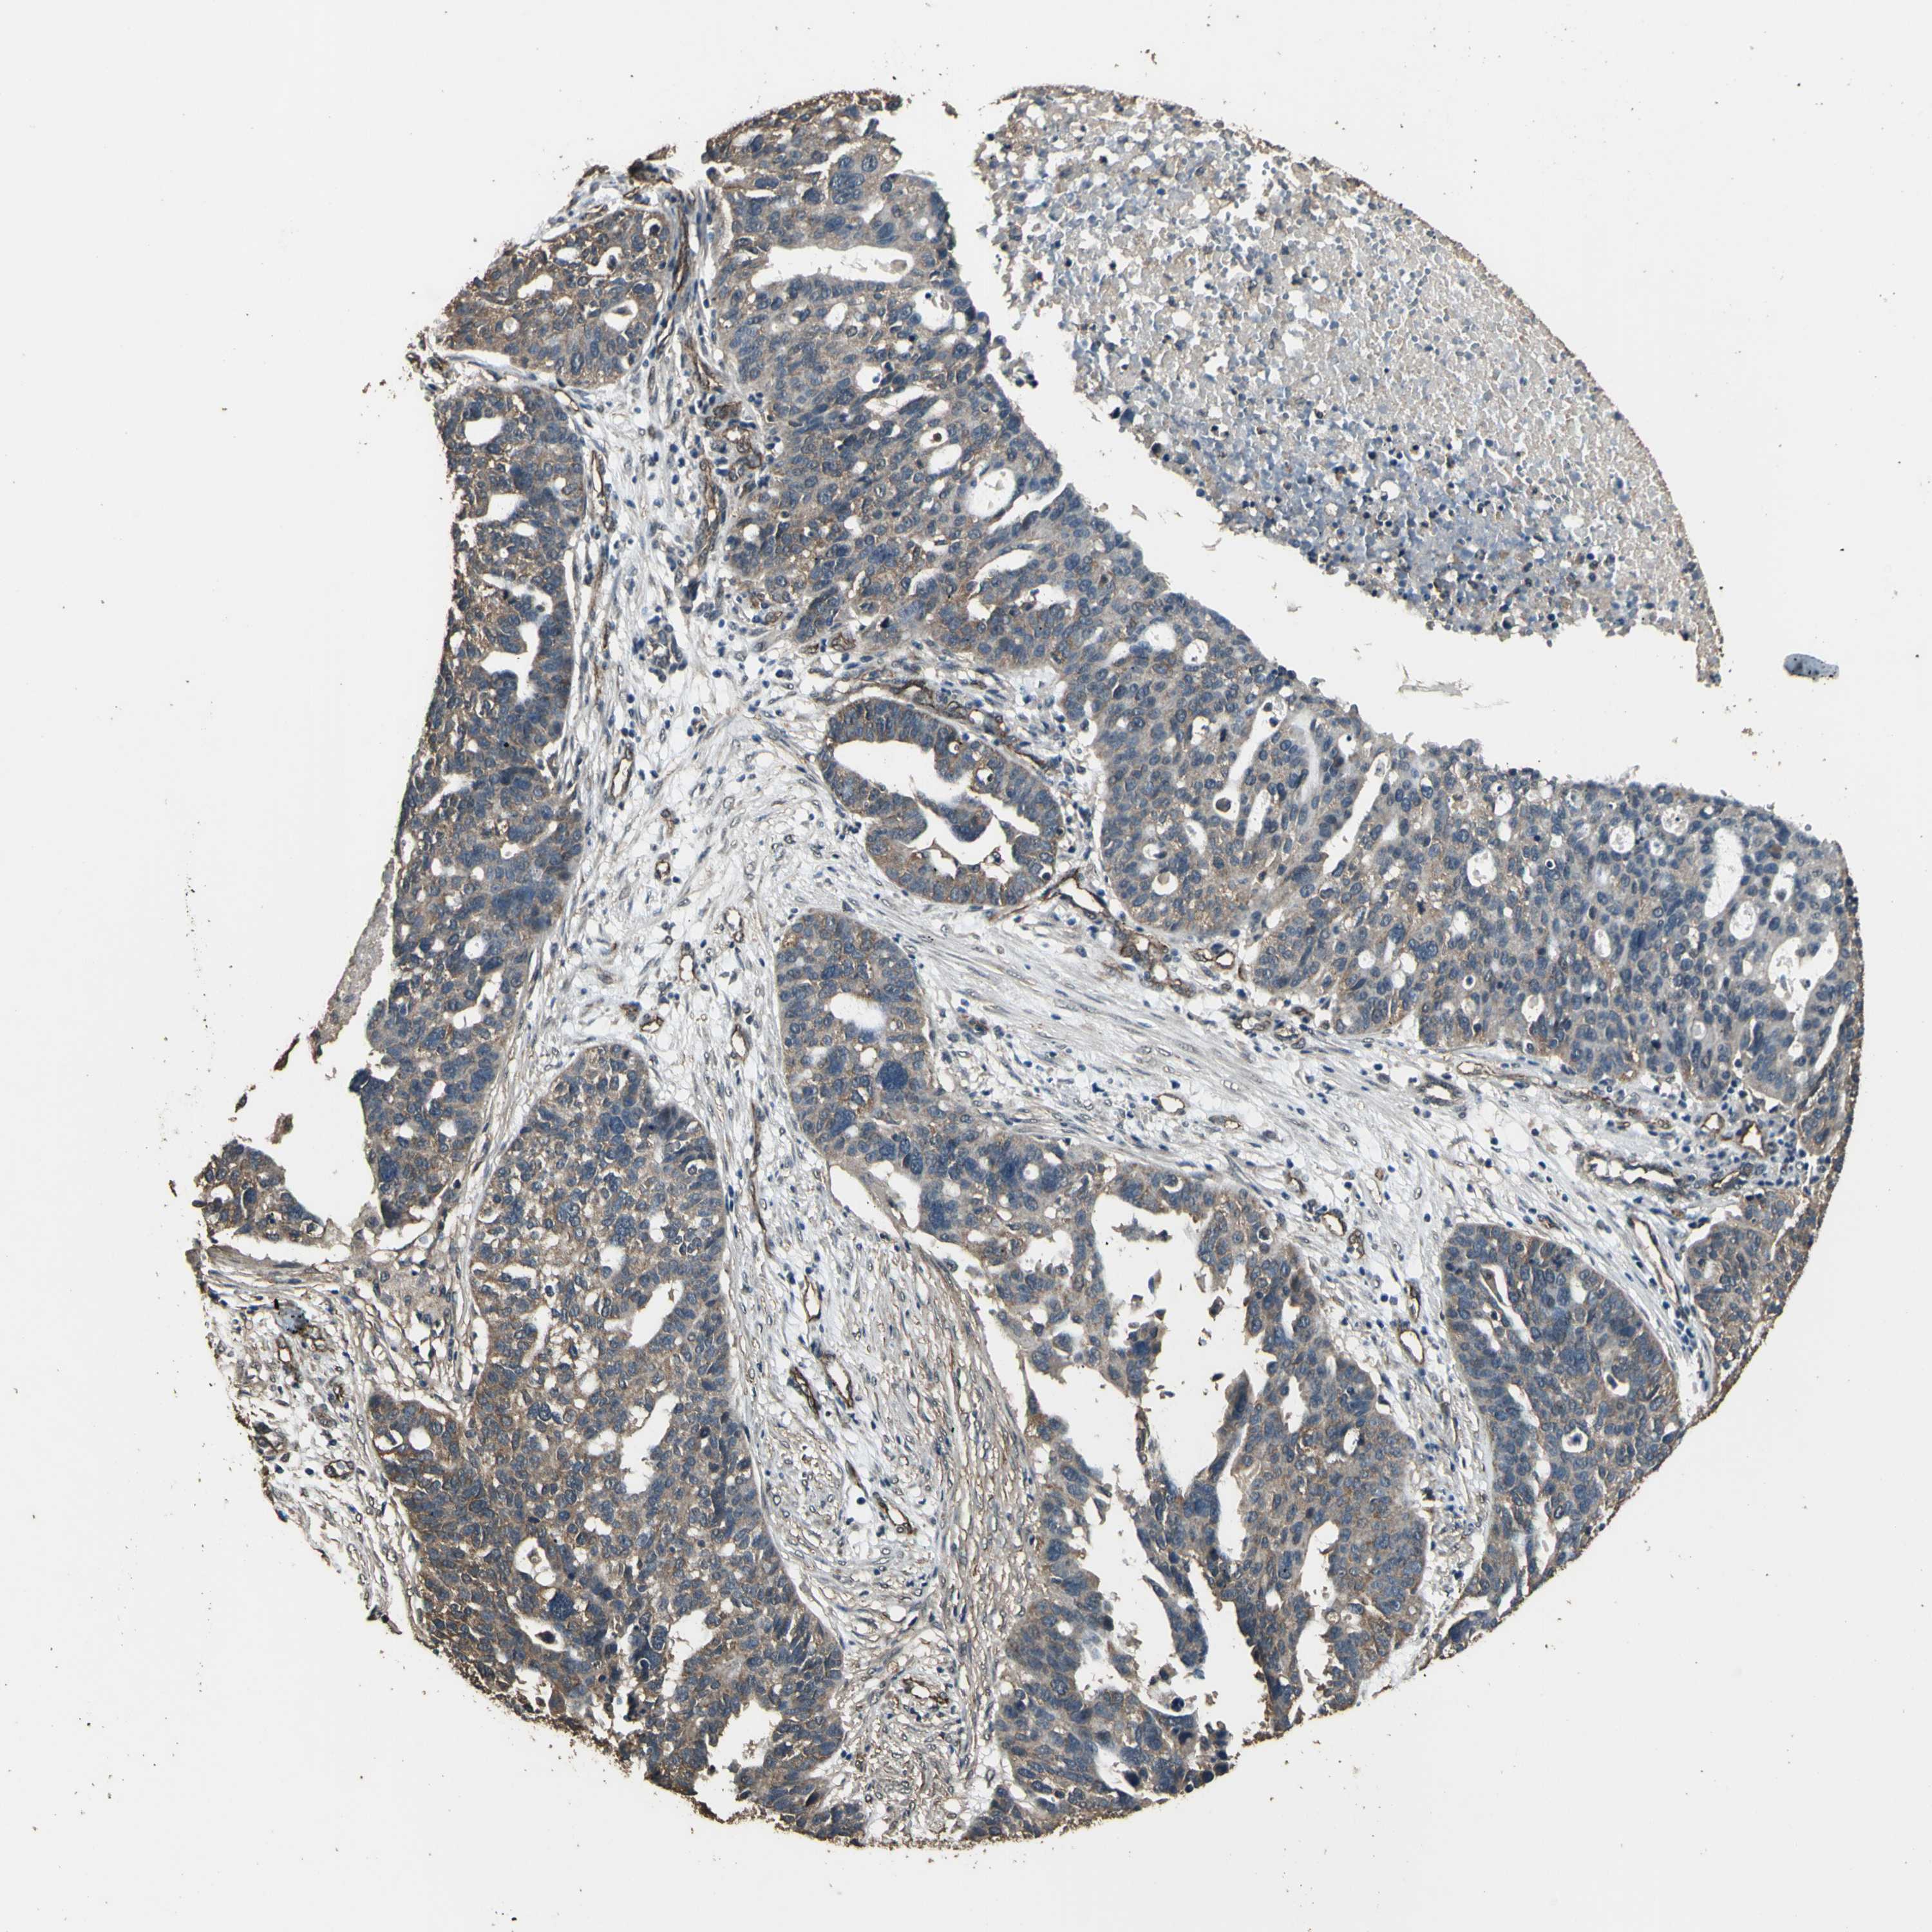

OVARIAN CANCER - Protein expressioni

A mouse-over function shows sample information and annotation data. Click on an image to view it in a full screen mode. Samples can be filtered based on level of antibody staining by selecting one or several of the following categories: high, medium, low and not detected. The assay and annotation is described here.

Note that samples used for immunohistochemistry by the Human Protein Atlas do not correspond to samples in the TCGA dataset.

Antibody stainingi

Antibody staining in the annotated cell types in the current human tissue is reported as not detected, low, medium, or high, based on conventional immunohistochemistry profiling in selected tissues. This score is based on the combination of the staining intensity and fraction of stained cells.

Each image is clickable and will lead to virtual microscopy that enables deeper exploration of all samples and also displays staining intensity scores, fraction scores and subcellular localization as well as patient and tissue information for each sample.

Antibody CAB011232

Staining

High

Medium

Low

Not detected

Intensity

Strong

Moderate

Weak

Negative

Quantity

>75%

75%-25%

<25%

None

Location

Nuclear

Cytoplasmic/membranous

Cytoplasmic/membranous,nuclear

Cystadenocarcinoma, serous, NOS

Carcinoma, endometroid

Cystadenocarcinoma, mucinous, NOS

Carcinoma, NOS